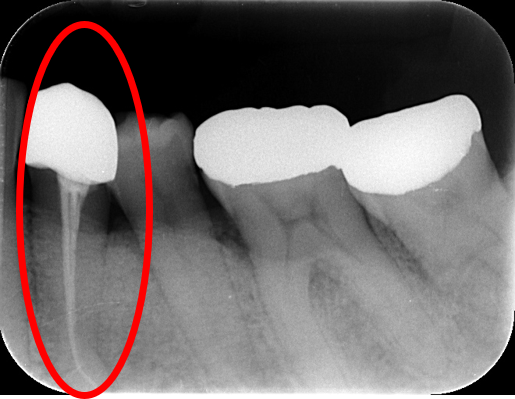

7. レントゲン写真で状態を確認する

6. レントゲン写真で状態を確認する